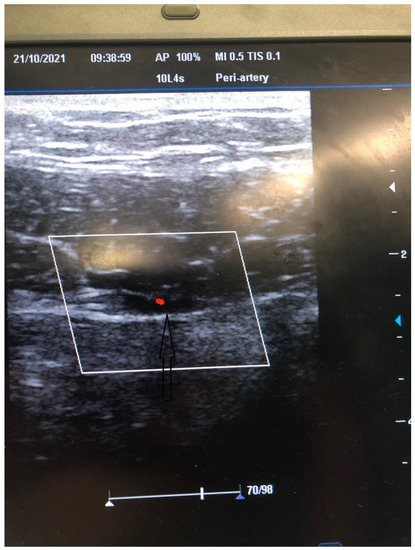

Figure 3.

US Doppler evaluation of the course of the inferior epigastric artery.